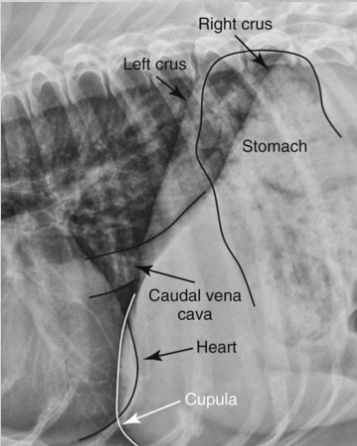

Differences between Right and left lateral thorax views:

A

In right lateral:

the diaphragmatic crura are parallel (in left, they form a V)

in right lateral, the caudal vena cava merges with the cranially positioned crus and with the caudal when its left lateral

left lung is seen better in right lateral

heart more egg-shaped in right lateral, rounder in left.

In left lateral: blood vessels of cranial lobes are easier to differentiate.

thoracic lymph nodes may be seen in right lateral but rarely ever in left lateral.